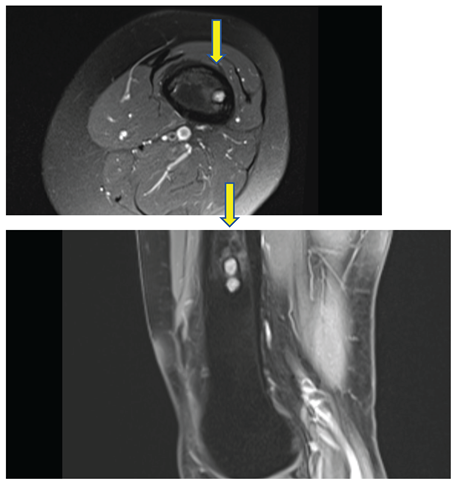

See Figure 4. and 5.

PD weighted image, axial and sagittal - sharply demarcated lesion with sclerotic border, high signal intensity in T2 i PD, low in T1, thickened cortical bone, without agressive periosteal reaction.

Given the prolonged interval since her last imaging evaluation, modern radiologic investigations were conducted. MRI and CT showed no abnormalities in the knee's soft tissues, but did reveal focal grade 2 patellar chondromalacia and minimal effusion in the suprapatellar recess. Importantly, four distinct lesions were identified in the left femoral diaphysis: three sharply demarcated round lesions (7-9 mm), and one subcortical lesion with sclerotic margins and imaging characteristics (low T1 signal, mixed T2 and PD signal with chondroid/fibrous components) consistent with residual CMF.

These lesions showed no signs of biological activity and were considered residual findings from childhood CMF. A follow-up MRI in three months was recommended to monitor potential changes.

This distinction is clinically significant. The lesions identified on MRI and CT were small, sharply demarcated, subcortical in location, and surrounded by sclerotic margins, without signs of cortical breakthrough or soft tissue invasion. Their imaging characteristics-low signal on T1 and mixed or intermediate signal on T2 and PD sequences-are consistent with CMF. Importantly, there was no peri-lesional edema or enhancement to suggest active inflammation or growth. Given the patient’s long symptom-free interval and excellent functional status, the current findings are most consistent with residual, inactive lesions rather than true recurrence. To further assess the metabolic activity of the lesions, a low density PET/CT scan was performed. The results showed no significant fluorodeoxyglucose (FDG) uptake in the femoral lesions, which strongly supports the interpretation that these are quiescent residuals rather than active or recurrent tumor tissue. Although CMF is typically a tumor of low metabolic activity, PET/CT can serve as a useful adjunct in ambiguous cases-especially when MRI findings are indeterminate or when clinical suspicion persists. The absence of FDG activity in this case provided additional reassurance and justified a conservative management approach with short-interval follow-up imaging. This case illustrates that not all post-treatment CMF lesions require excision, especially when they remain asymptomatic and radiologically stable. The patient’s current symptoms were unrelated to tumor recurrence and were instead due to pes anserinus bursitis—confirmed by clinical improvement following targeted corticosteroid injection. To our knowledge, only two cases of CMF have been reported in Croatia to date, both involving atypical locations-the mandible and the second metacarpal bone [